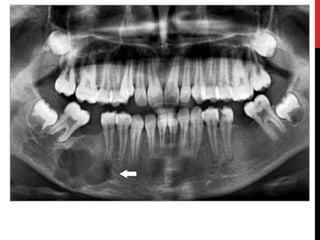

MULTIPLE MYELOMA

• Most common primary neoplasm of the skeletal system.

• Malignancy of plasma cells.

• Underlying pathology → Expansion of a single line of

plasma cells that replace normal bone marrow and produce

monoclonal immunoglobulins.

• Age: 60-65 years

• Sex: males> females

• More common among black people

• Site: mandible> maxilla

• Number of lytic foci or diffuse demineralization.

• Anemia, azotemia, hypercalcemia, recurrent infection.

• Extramedullary plasmacytoma- tonsils, nasopharynx, or

paranasal sinuses